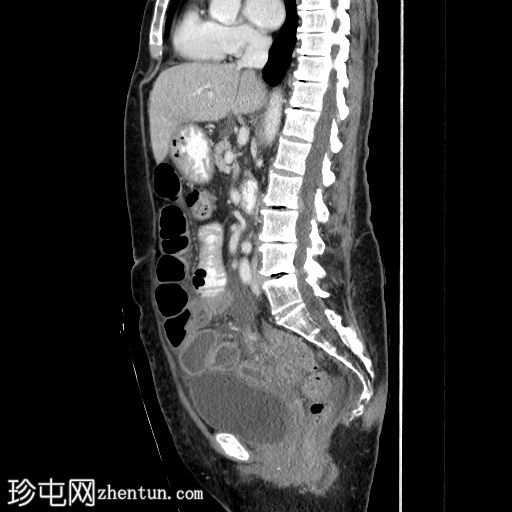

矢状位增强扫描(门静脉期)

回肠末端长段狭窄,管腔狭窄,肠壁增厚/不规则,几乎延伸至回盲瓣。上游小肠节段扩张和粪便样改变,无重度梗阻。少量腹水。子宫切除术史。骶骨因放射治疗而相对脱钙。

病例讨论

典型的慢性放射性肠炎表现,导致狭窄和部分小肠梗阻。狭窄的

影像

表现多种多样,与放射野血管损伤引起的慢性缺血(闭塞性动脉内膜炎)有关。即使没有相应的临床病史,如果发现子宫缺失,骶骨和下腰椎呈脱矿质(更透亮)外观,也可以怀疑这种诊断。